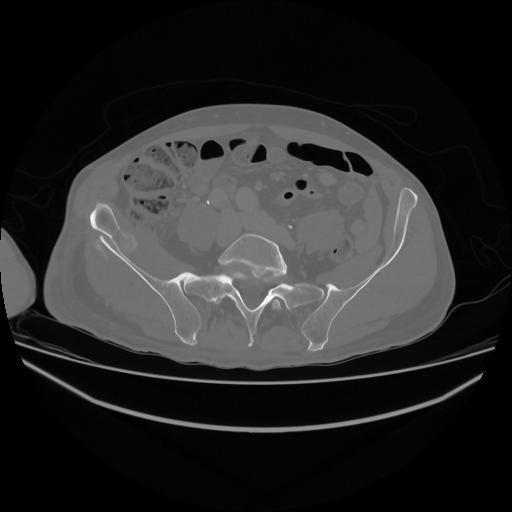

5 CUERPO,CE,Vol,1.0,CUERPO,,